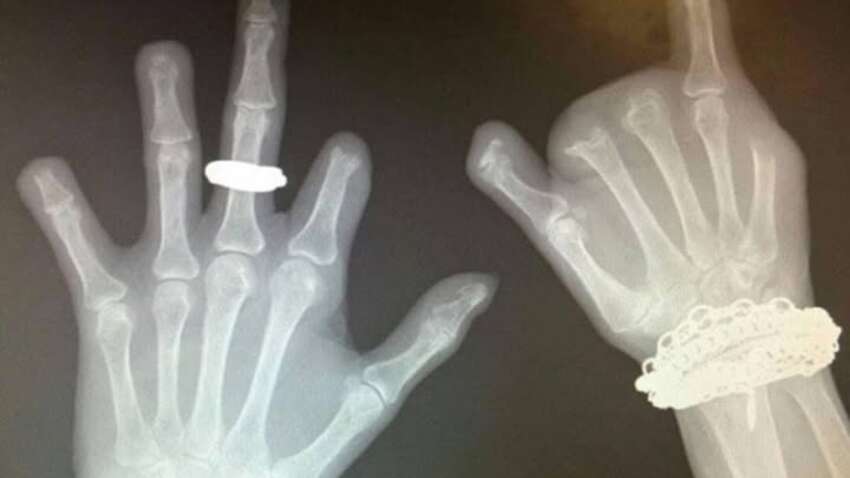

Медики показали вражаюче фото та клінічний випадок, який ще раз доводить: звичка гризти нігті — це не просто невинний жест нервозності. У пацієнтки, яка роками страждала на тяжку форму оніхофагії, постійне пошкодження нігтів переросло у хронічні рани, бактеріальні інфекції та зрештою — остеомієліт. Ураження кісток було настільки серйозним, що хірургам довелося ампутувати кілька фаланг пальців. На рентгенівських знімках чітко видно деформації та відсутність частини кісток. Про це повідомляє "Типовий медик".

Наслідки тяжкої оніхофагії: інфекції, деформації та ампутація кількох пальців.